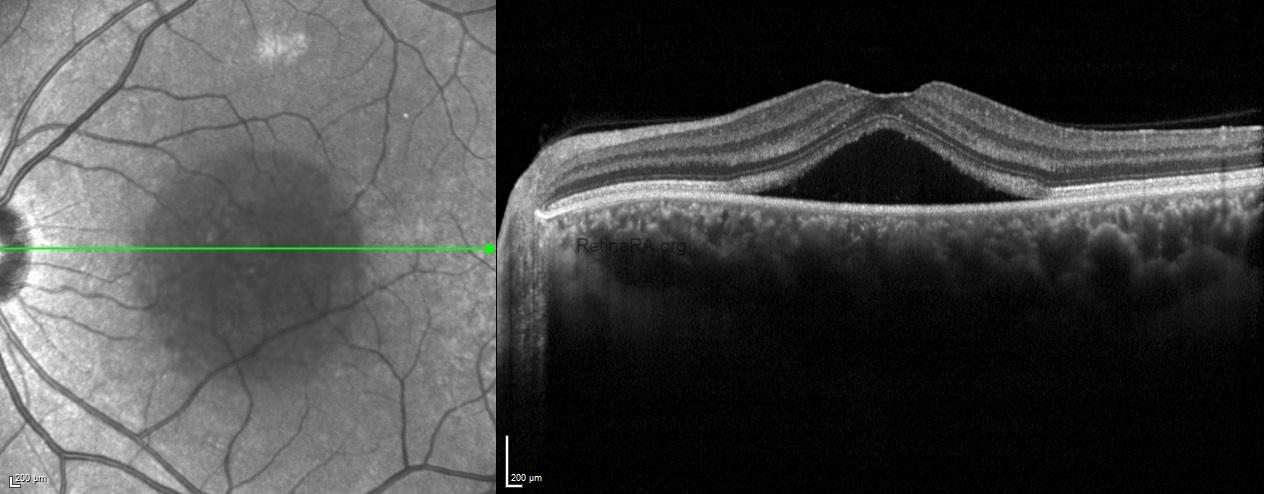

Enhanced depth imaging spectral domain optical coherecence tomography scans exhibited choroidal thickening bilaterally in addition to serous macular detachment in the left eye.

Fundus autofluorescence demonstrated hypoautofluorescence of the central macula due to the subretinal fluid in the left eye.